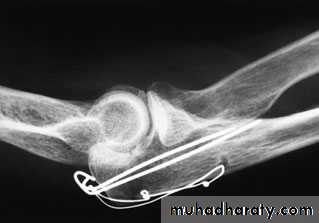

X-ray

3-Displaced transverse fractures can be held only by splinting the arm absolutely straight – but stiffness in that position would be disastrous. Operative treatment is therefore strongly recommended. The fracture is reduced and held by tension band wiring. Oblique fractures may need a lag screw, neutralised by a tension band system or plate.